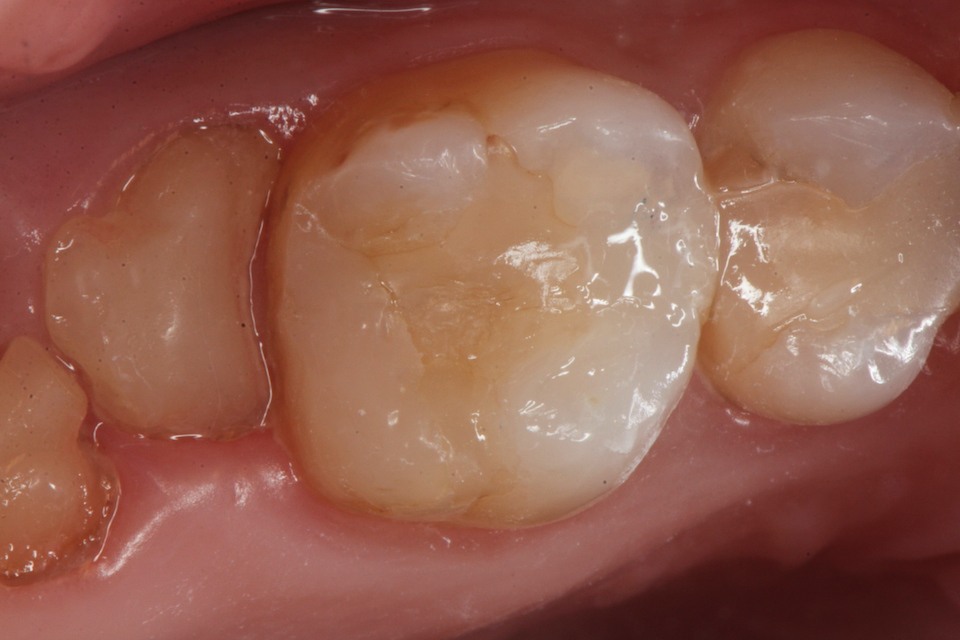

下顎7番の頬側歯茎部カリエスの原因 2025.06.04